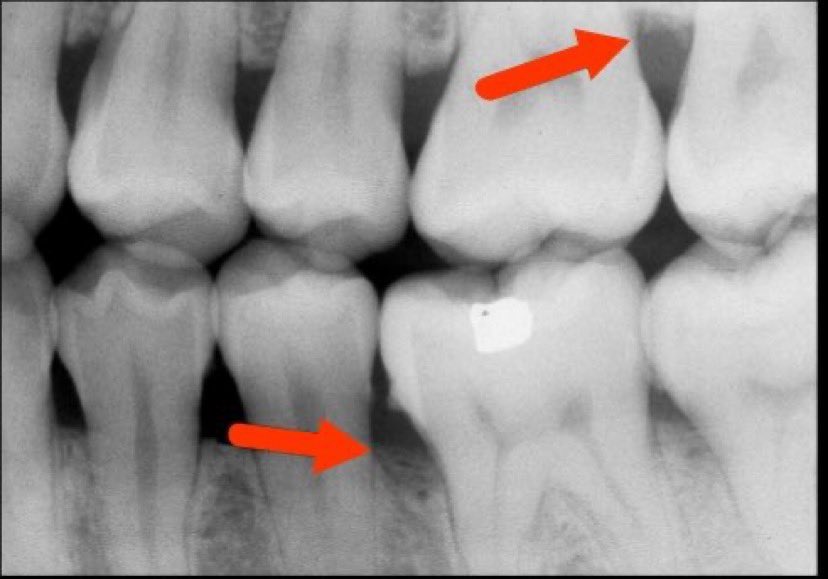

التهاب اللثة العميق(مرحلة٢):

-تآكل بسيط في اطراف العظم الداعم للآسنان وقد(غالبا)يكون مصحوب بعلامات من التهاب اللثة الخارجي

اعراضه قد تشابه المرحلة (١) وقد لا يكون ظاهرا

-يمكن علاجه إذا اكتشف باكرا وإيقاف تقدمه.